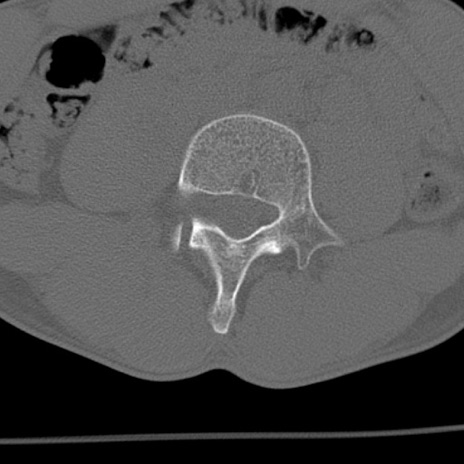

症例3 腰椎CT(横断像)

腰椎CT